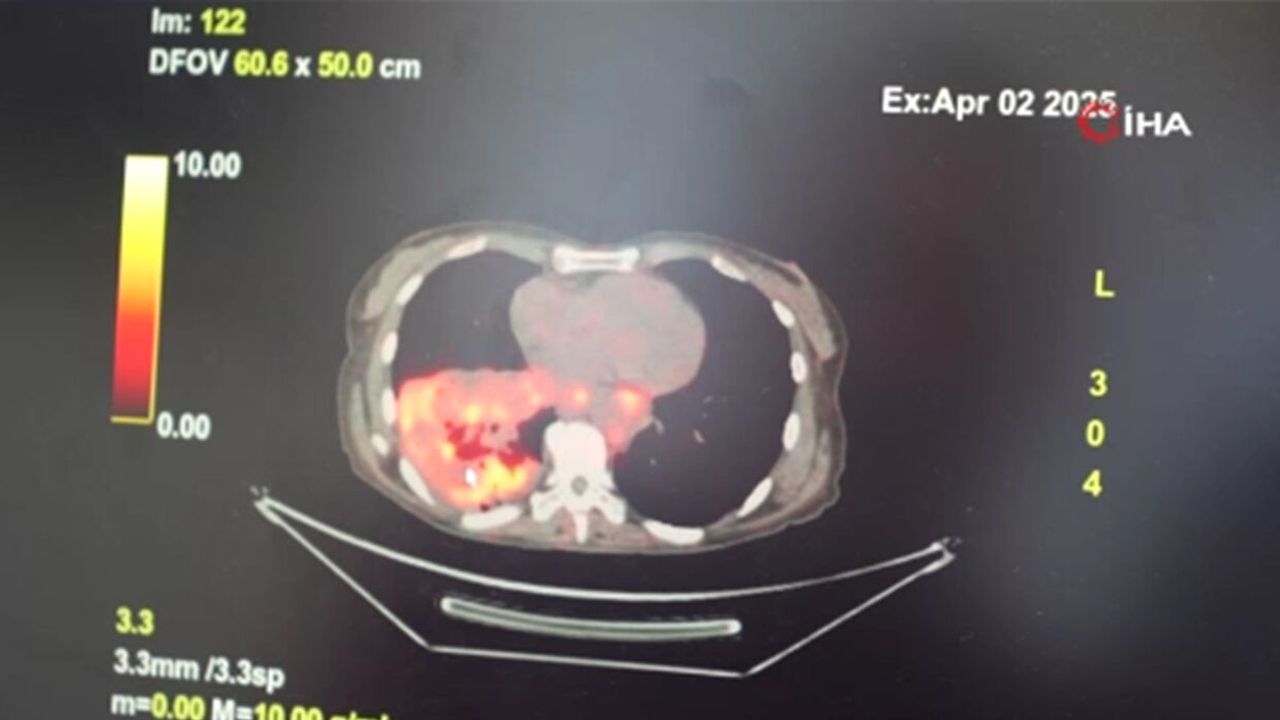

GÖĞÜS HASTALIKLARI UZMANI PROF. DR. ŞEVKET ÖZKAYA, SON YILLARDA SİGARA KULLANMAYAN BİREYLERDE DE AKCİĞER KANSERİ VAKALARININ DİKKAT ÇEKEN BİR ORANDA ARTTIĞINI BELİRTEREK, ÖZELLİKLE KADINLARDA GÖRÜLEN ADENOKARSİNOM TİPİ AKCİĞER KANSERİNİN ARTIŞ GÖSTERDİĞİNE DİKKAT ÇEKTİ. BU KONUDA YAPILAN SON ARAŞTIRMALARA DEĞİNEN ÖZKAYA, AKCİĞER KANSERİ TEŞHİSLERİNİN YAKLAŞIK YÜZDE 20'SİNİN HİÇ SİGARA İÇMEMİŞ BİREYLERDE KONDUĞUNU SÖYLEDİ. (FURKAN ABREK ÜNAL/SAMSUN-İHA)Göğüs Hastalıkları Uzmanı Prof. Dr. Şevket Özkaya, son yıllarda sigara kullanmayan bireylerde de akciğer kanseri vakalarının dikkat çeken bir oranda arttığını belirterek, özellikle kadınlarda görülen adenokarsinom tipi akciğer kanserinin artış gösterdiğine dikkat çekti. Bu konuda yapılan son araştırmalara değinen Özkaya, akciğer kanseri teşhislerinin yaklaşık yüzde 20'sinin hiç sigara içmemiş bireylerde konduğunu söyledi.

Dünyanın en prestijli tıp dergilerinden yayımlanan bir araştırma üzerinde açıklama yapan Prof. Dr. Şevket Özkaya, araştırmaya göre, sigara içmeyenlerde en sık görülen tür olan akciğer adenokarsinomu, kadınlarda akciğer kanserlerinin yaklaşık yüzde 60’ını oluşturduğunu söyledi. Prof. Dr. Özkaya, sigara dışındaki risk faktörlerinin başında radon gazının geldiğine dikkat çekerek, "Radon gazı, evlerimizde farkında olmadan soluduğumuz, renksiz, kokusuz, tatsız ve radyoaktif bir gazdır. Müsaade edilen değerlerin üzerinde solunduğunda akciğer kanseri riskini artırıyor. Radon gazı özellikle taş, toprak ve çimento gibi yapı malzemelerinde doğal olarak bulunuyor. Bu maddelerden ortama sürekli yayılan gaz, solunum yoluyla akciğerlere ulaşıyor" ifadelerini kullandı. Evlerin yapıldığı arazilerde bulunan doğal uranyumun radona dönüşmesiyle bu gazın evlerin zemin katlarından iç ortama sızabildiğini vurgulayan Özkaya, bu durumun bölgeden bölgeye ve ülkeden ülkeye farklılık gösterdiğini kaydetti. Özellikle soğuk ve rüzgarlı havalarda, evin iç basıncının düşük, dış basıncın yüksek olması nedeniyle radon gazının iç ortamdaki oranının arttığını ifade etti.